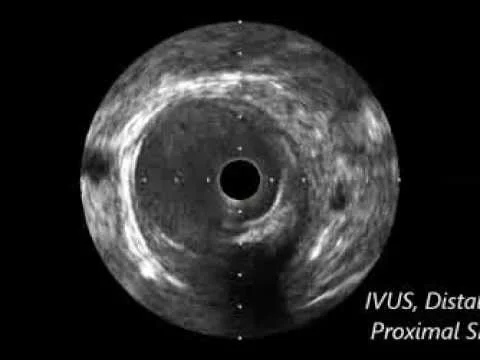

IVUS Diagnostic for Distal SFA